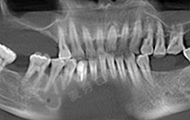

按照预约的时间,今天早早就来到了麦芽口腔,通过德国KAVO锥形束CT检查缺牙处牙槽骨的骨质密度、厚度,并分析牙周口腔健康后,郑院长根据我牙槽骨数据和口腔健康情况分析,采用MAC数字化精确种植,来恢复牙咬合功能的种植方案。

首先通过数字化精确影像采集测量患者牙床的骨质密度、牙槽骨本身的高度、宽度等条件,设计最佳力学种植点,同时发现神经血管,做到心中有数。在手术过程中,通过实时导航技术,控制种牙的深浅、避开口内危险区域,不仅减小了创口,平均种1颗牙耗时10分钟,减少了肿痛和出血量,缩短了种植牙时间,种植位置更准确,种植成功率更高,帮助了无数害怕疼痛的缺牙患者,轻松拥有一口好牙。